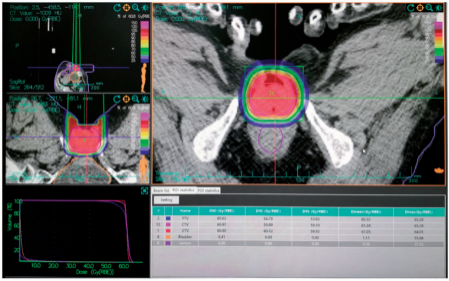

Figure 3. Carbon ion radiotherapy target and dose distribution.

CIRT was delivered at a 60.8-Gy RBE-weighted dose in 16 fractions with a 190-MeV/U carbon ion beam, once daily, five times per week (Monday to Friday) for 22 days using one vertical portal (Figure 3).